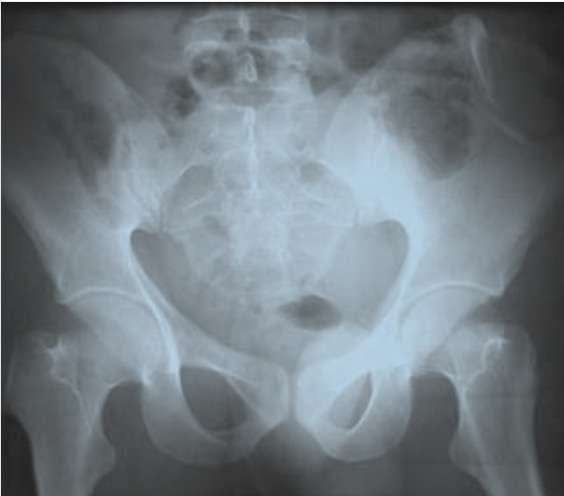

At the hospital, stripped naked of my garments with scissors, after X-Rays I’m told I’ve fractures in my hip and a broken bone in my left hand. The latter is a spiral fracture which narrowly avoids being wired up. I’m a very lucky man. The consultant compares my hip to a Polo mint. How often can you crack one side without the whole thing splitting in two? I’ve cracked the iliac crest, which is the ‘wing’ of the hip – the part that would sit above the belt line. Amazingly, I’ve avoided damaging the femur joint, or splitting my pelvic girdle in two. There is a crack snaking its way through towards the sacroiliac joint, but I am told my hips are stable and I should try to get onto crutches.